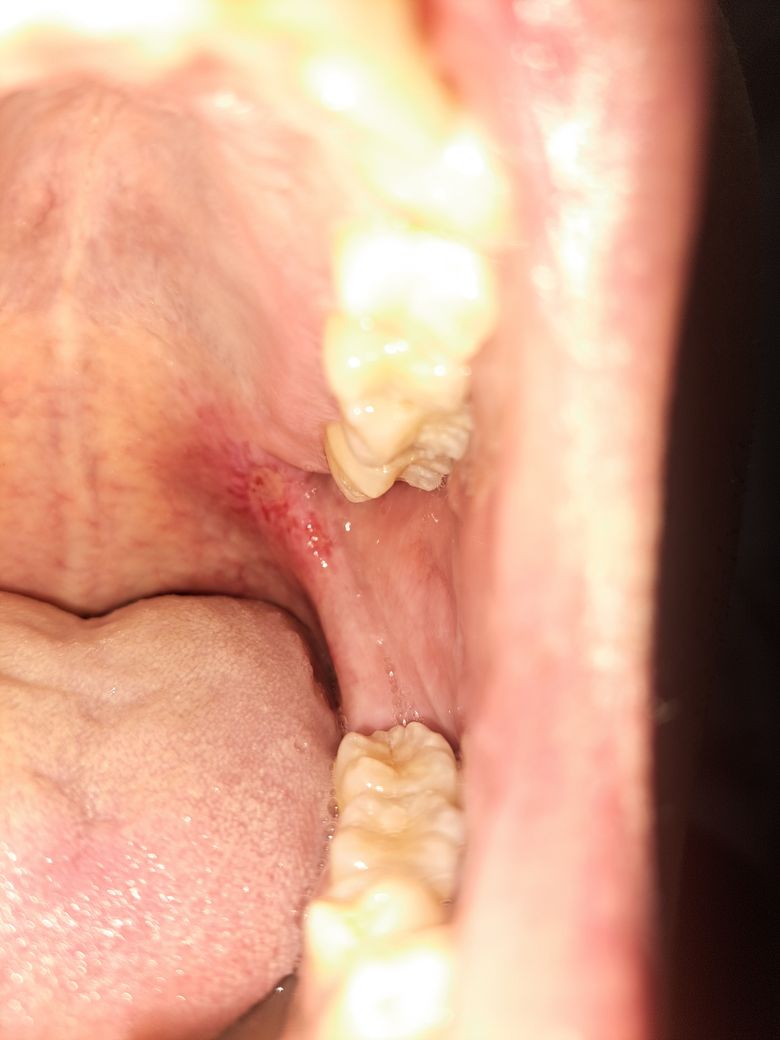

첨부사진과 같은 염증이 발병한지

2주정도가 되었습니다

사진상 보이는 붉은 상처가

구강암 조직검사를 받아야 하는지

구강암은 아니신거 같습니다. 구강내 상처가 잇는경우 침때문에 상처가 잘 낳지 않습니다. 조금더 기다려보시는게 좋을것같습니다.